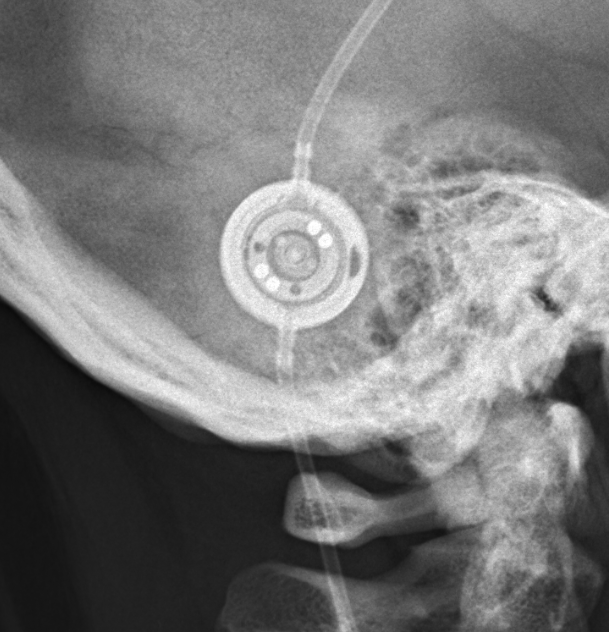

Programmable Valves

Medtronic Strata NSC

Medtronic Strata NSC valves are adjustable csf shunt valves.